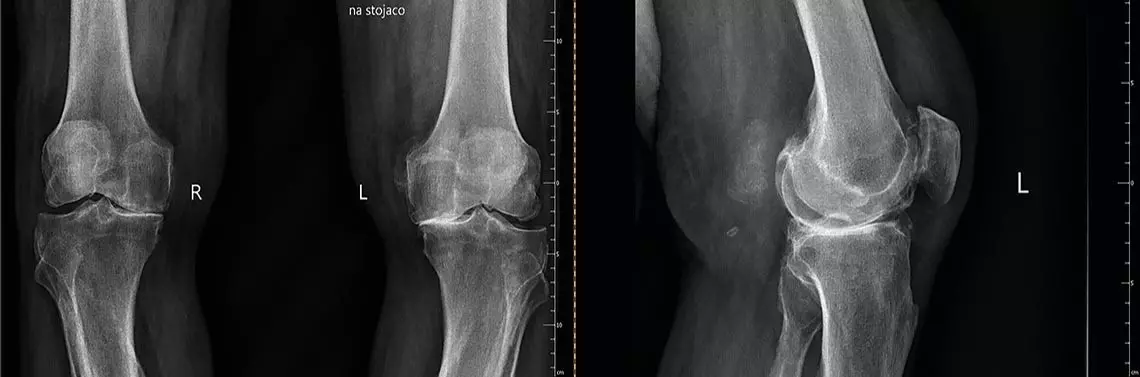

• choroba zwyrodnieniowa (zdj. 1).

Zdj. 1. Choroba zwyrodnieniowa

Choroba zwyrodnieniowa stawów to złożony i skomplikowany powolny proces prowadzący na przestrzeni lat do dysproporcji w procesie tworzenia i degeneracji chrząstki stawowej. Szybko postępujący proces chorobowy w znacznym stopniu przyczynia się do zainfekowania zdrowych struktur wewnątrzstawowych.